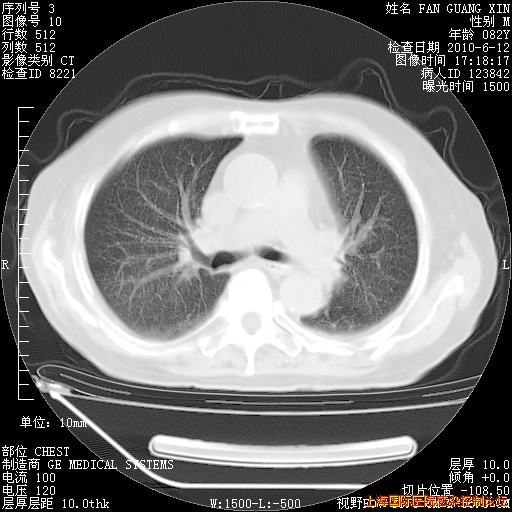

补发6月12日肺部CT肺窗

6月12日肺窗